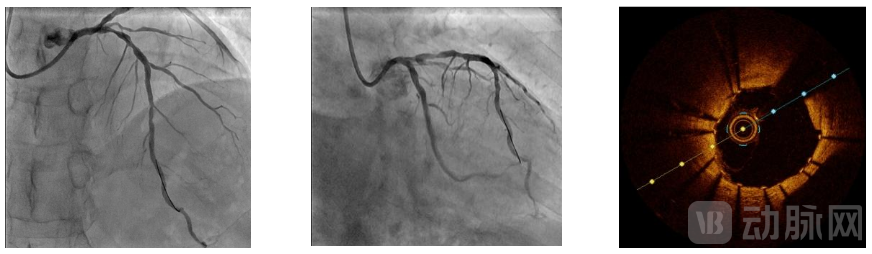

介入治疗靶病变为前降支中段,6F EBU3.5指引导管送至左冠口,将导丝分别送至前降支及第一对角支远段,于前降支送入OCT导管回撤行OCT检查可见脂质斑块,最小管腔面积为1.9mm²,遂决定进一步行前降支介入治疗。术中使用Scoreflex TRIO 2.5*15m球囊于病变处以8atm*10秒扩张,复查造影残余狭窄改善明显,残余狭窄小于30%,TIMI血流III级;于病变处植入支架一枚以10atm*10秒扩张释放,取非顺应性球囊于支架内16atm*10秒后扩张塑形,复查造影提示支架扩张满意,无残余狭窄,远端TIMI血流III级。

复查OCT提示前降支支架扩张满意,贴壁良好,支架膨胀率90%,手术成功。

术终患者血压138/82mmHg,心率64次/分,无并发症发生。